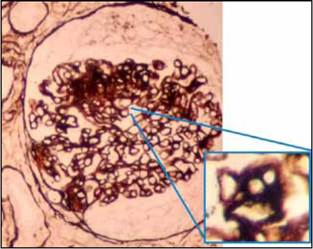

Se confirmó el diagnóstico de síndrome nefrótico y se decidió solicitar biopsia renal que reportó hallazgos de nefropatía membranosa con un componente agudo necrosante de proliferación extracapilar (Figuras 1-3).

Por otro lado, la evidencia histopatológica de proliferación de células epiteliales viscerales o parietales en el espacio de Bowman se conoce como proliferación extracapilar. Cuando el daño glomerular es muy severo, se asocia con ruptura de la pared capilar o de la cápsula de Bowman lo que permite el ingreso de proteínas plasmáticas y material inflamatorio al espacio de Bowman, configurando una forma de crescencia o medialuna, hallazgo que generalmente implica un deterioro acelerado de la función renal en el contexto clínico de una glomerulonefritis rápidamente progresiva, generalmente asociada a vasculitis, enfermedad de Goodpasture o a otras glomerulonefritis agudas y severas de cualquier otra etiología 5.

Finalmente, el caso descrito no cumple criterios de LES, tiene ANCA y anticuerpos antimembrana basal negativos, con ausencia de tinción lineal en membrana basal glomerular (anti- IgG y anti-C3) en estudio de inmunofluorescencia. En este sentido, surge la hipótesis de si se trata de una expresión anormal de una glomerulopatía membranosa o si por el contrario es una glomerulopatía membranosa a la que se adiciona una glomerulonefritis pauci-inmune ANCA negativo. El tratamiento inmunosupresor establecido de forma temprana fue determinante para una evolución adecuada.